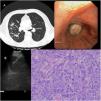

Our case is a 75-year-old man, a former smoker who quit 10 years ago, came to the emergency room for a cough with purulent sputum without fever. A chest scan was performed where pulmonary consolidation with a patchy distribution was detected in LSD, LM, LID and LII, and bilateral pneumonia was diagnosed (Fig. 1 A). The patient was admitted to the ward for control and treatment.

In subsequent controls, there was little radiological improvement, so a bronchoscopy was performed to take samples. An endobronchial mass in the intermediate bronchus was discovered. A biopsy of the lesion resulted in necrotic material (Fig. 1B).

An endobronchial ultrasound (EBUS) was then performed for lymph node staging, with a negative (N0) result with a new biopsy where, once again, the material was necrotic but the bronchialaspiration was positive for squamous cell carcinoma (Fig. 1C).

A cryobiopsy of the lesion was performed due to the absence of sufficient histological material and a tumor with an angiocentric growth pattern was identified, composed of pleomorphic cells growing on a lax stroma. Part of the tumor cellularity exhibit an enlarged nucleus of ovoid morphology with central nucleolus and clear eosinophilic cytoplasms. Other fields show a fusiform cellularity with clear cytoplasms that are arranged on a desmoplastic stroma. Histological and immunophenotypic findings compatible with carcinosarcoma (Fig. 1D).